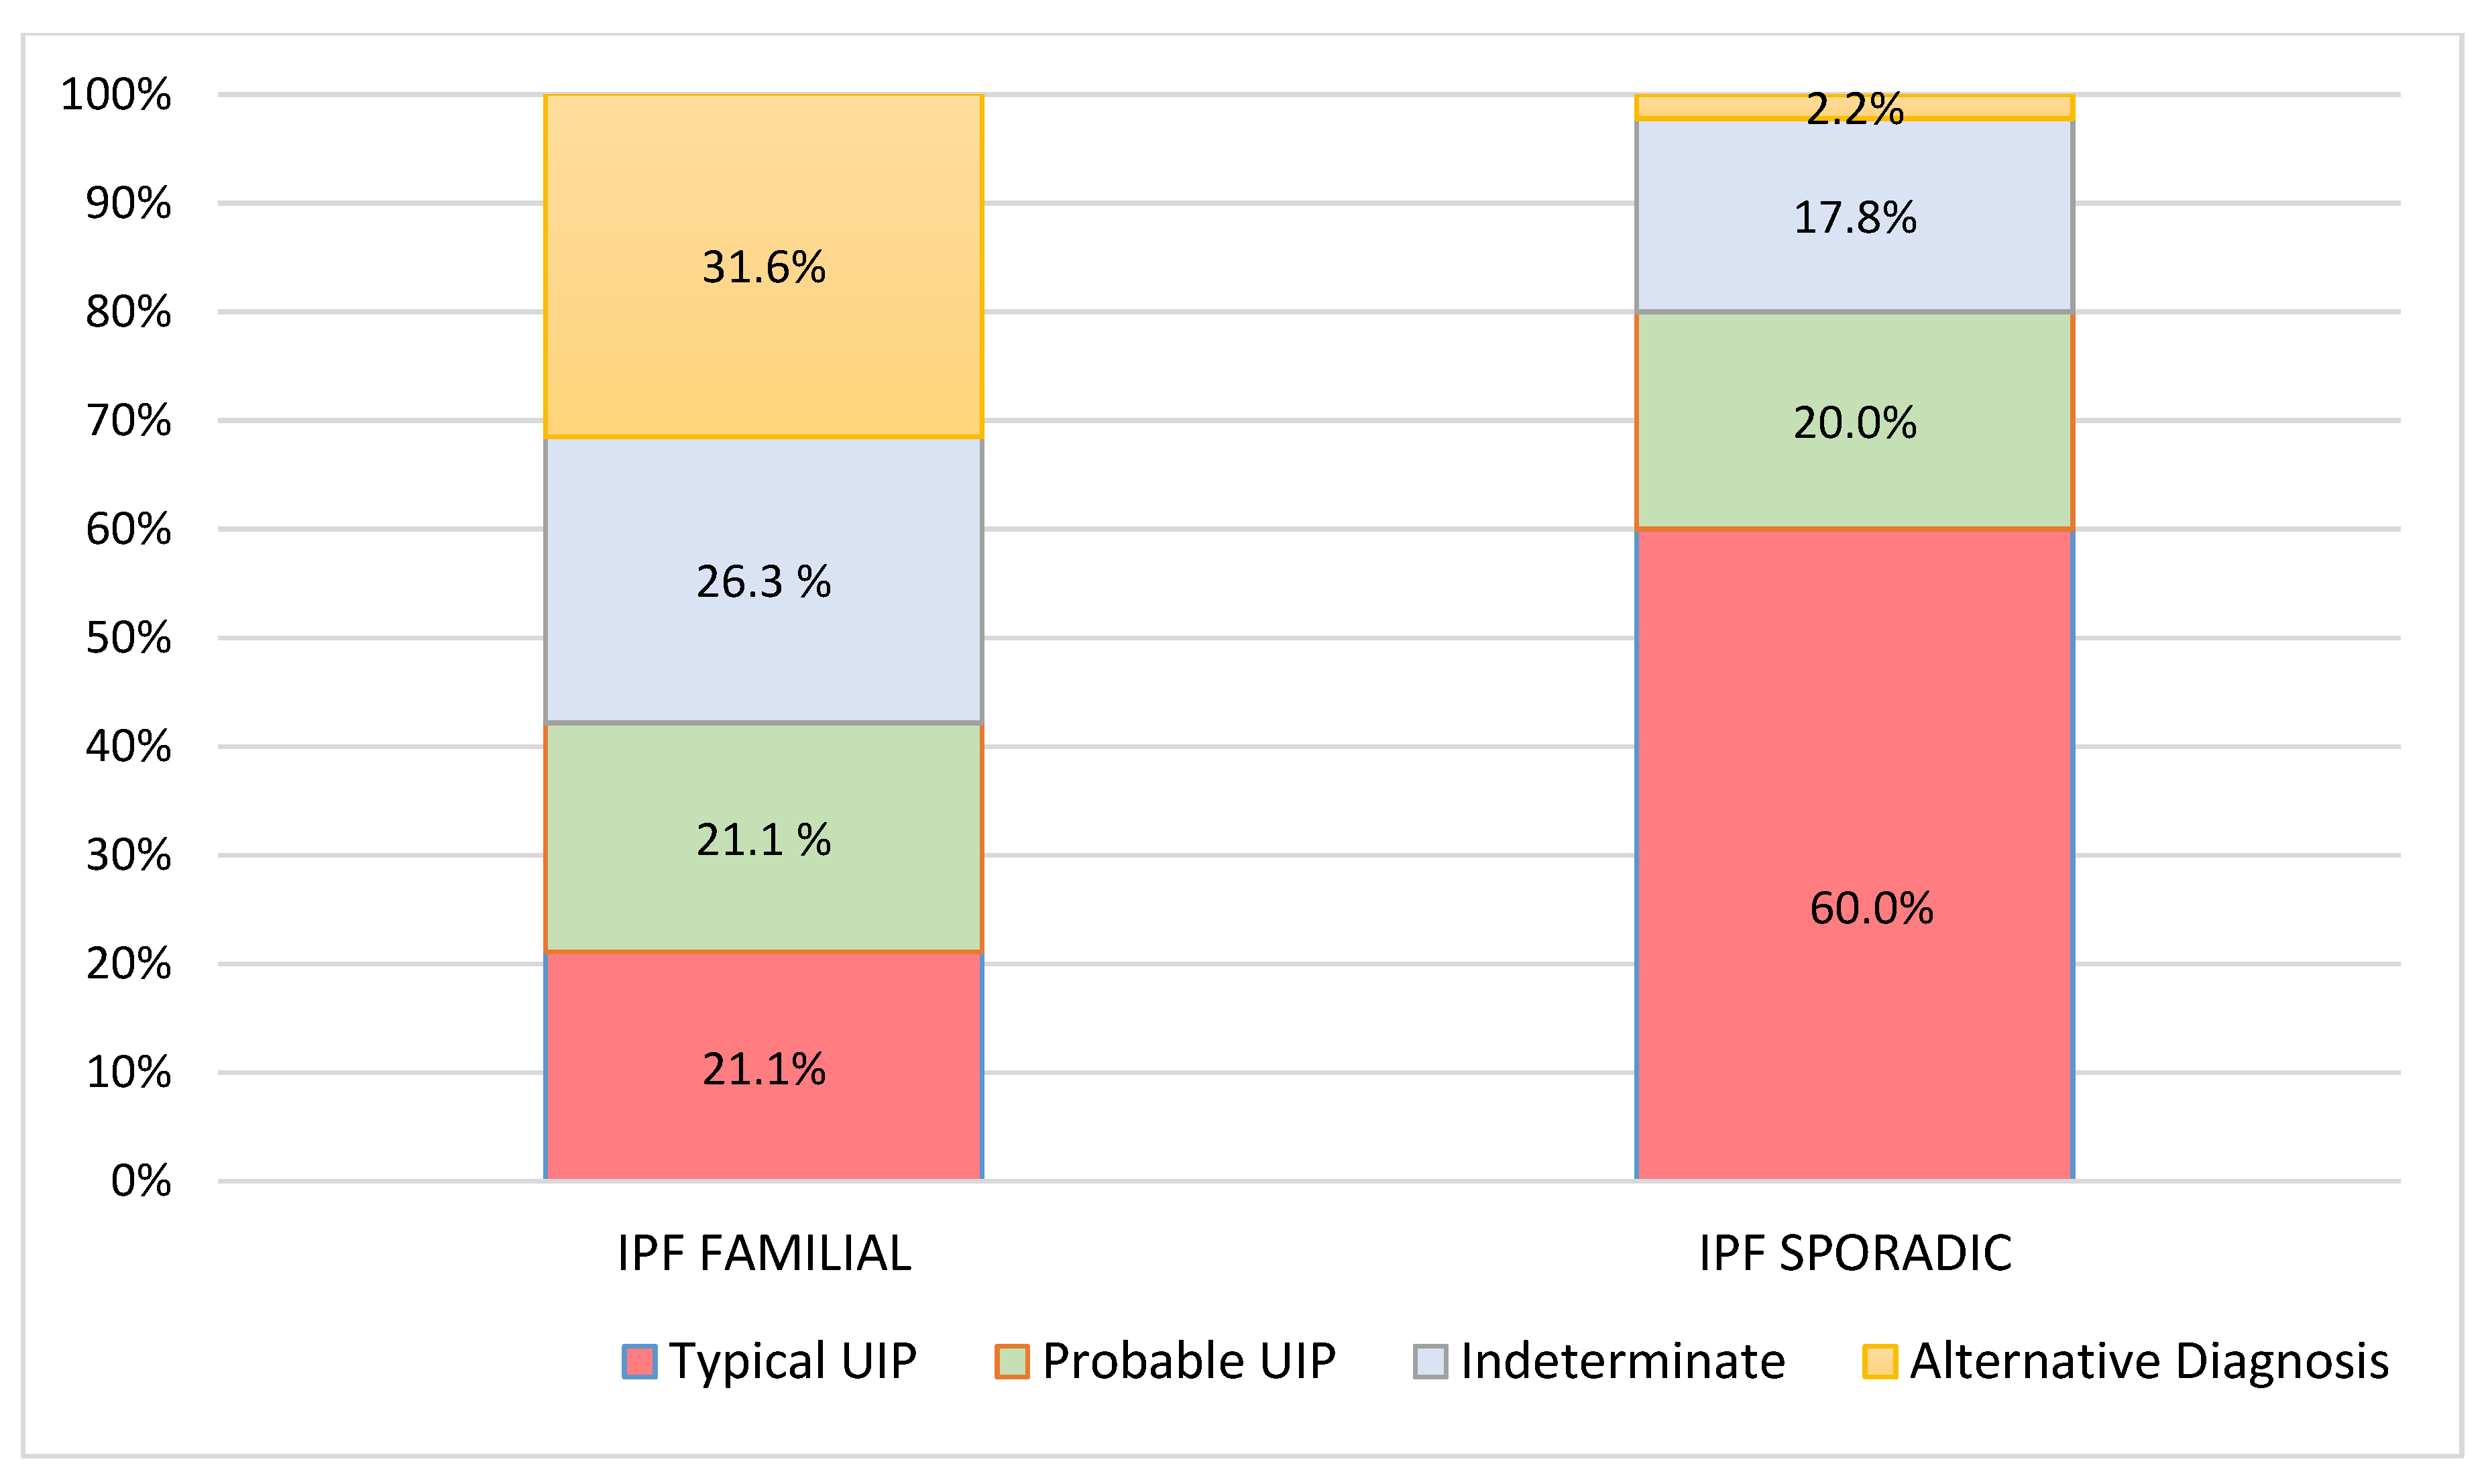

| Pattern at Diagnosis (N, %) | |||

| typical UIP | 4 (21.1%) | 27 (60.0%) | |

| probable UIP | 4 (21.1%) | 9 (20.0%) | 0.001 |

| Indeterminate | 5 (26.3%) | 8 (17.8%) | |

| Alternative Diagnosis | 6 (31.6%) | 1 (2.2%) | |

| Pattern at 2 years (N, %) | |||

| Typical UIP | 8 (42.1%) | 33 (75.0%) | 0.014 |

| Probable UIP | 4 (21.1%) | 7 (15.9%) | |

| Indeterminate | 1 (5.3%) | 2 (4.5%) | |

| Alternative Diagnosis | 6 (31.6%) | 2 (4.5%) | |